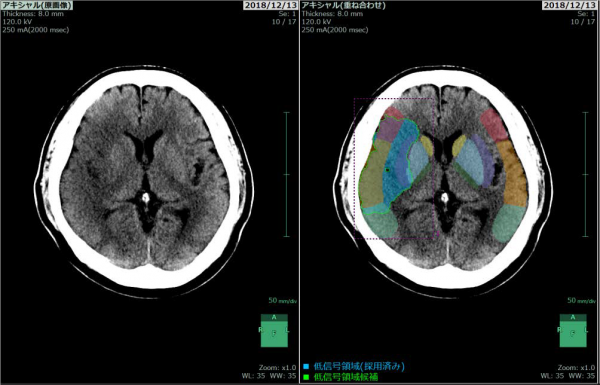

左:画像解析前、右:画像解析後

低信号領域(画像上、周囲と比べて黒っぽい領域)を強調して青色で表示する。

左 画像解析前

右 画像解析後

低信号領域の抽出結果(四角で囲った部分)と、10区域に分割した中大脳動脈領域を色分けして表示する。

ASPECTSの結果

中大脳動脈領域に低信号領域がない場合は10点、全区域に低信号領域がある場合は0点となる。この画像では9区域に低信号領域が広がっており、ASPECTSは1と算出されている。